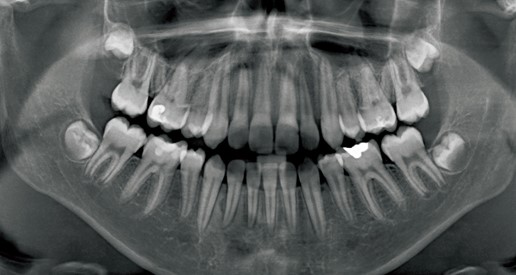

牙種植體通常是鈦替代物,可通過外科手術將其植入頜骨中並註入其中以獲得穩定的結果。他們再次擁有一整套牙齒,從而取代了不切實際,不安全的義齒使用。儘管假牙能夠提供具有完整牙齒組的外觀,但是使用它們會給特別是相鄰牙齒造成問題。此外,假牙很難使用,尤其是在需要使用膠水保持穩定的情況下。